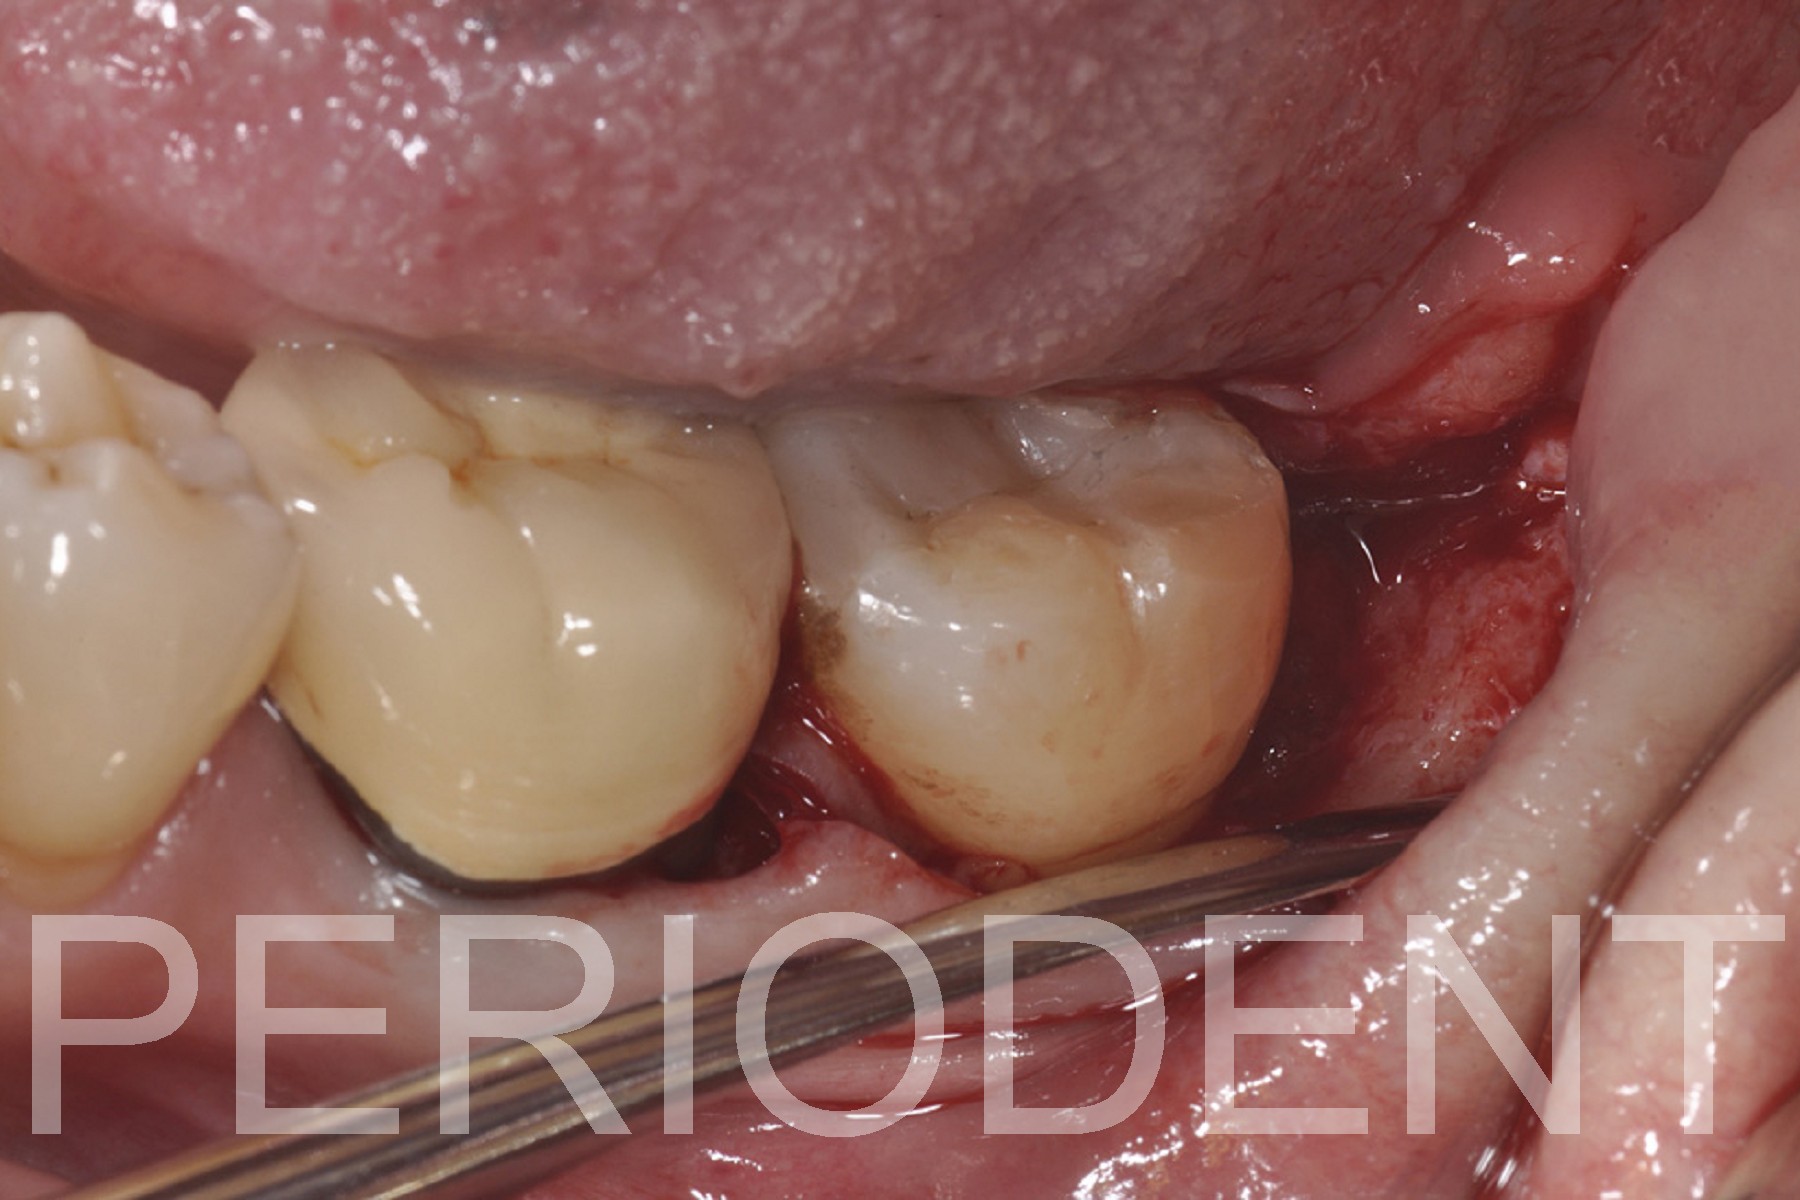

2015年進行distal wedge手術

2023年進行牙周再生手術